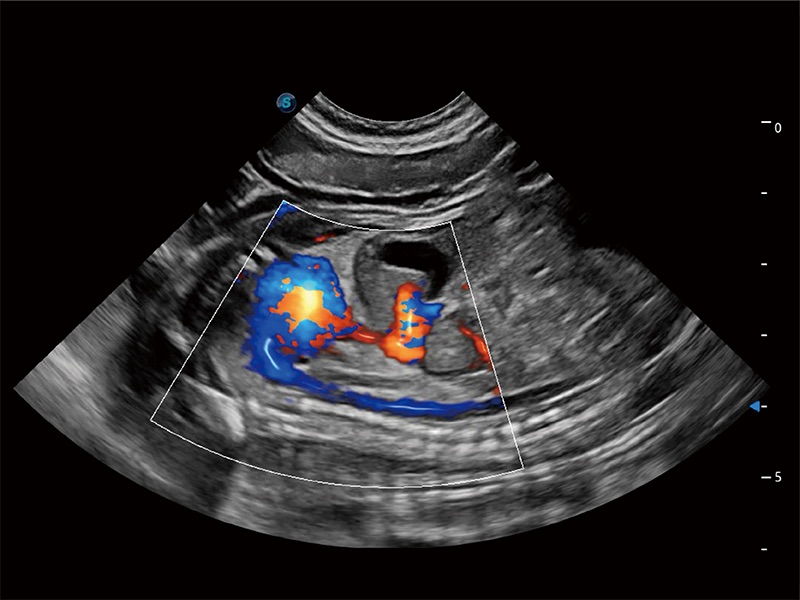

極大提升超低速微細(xì)血流的檢出能力,同時(shí)更精準(zhǔn)地濾除軟組織和超聲信號(hào),為獸用醫(yī)生提供以往無(wú)法通過(guò)常規(guī)血流獲得的疾病診斷信息。

在傳統(tǒng)二維血流成像的基礎(chǔ)上,呈現(xiàn)血流的立體感,具有動(dòng)感的生命力之美。即便是微小的血管也能輕松應(yīng)對(duì),提高了血流的視覺(jué)敏感性。